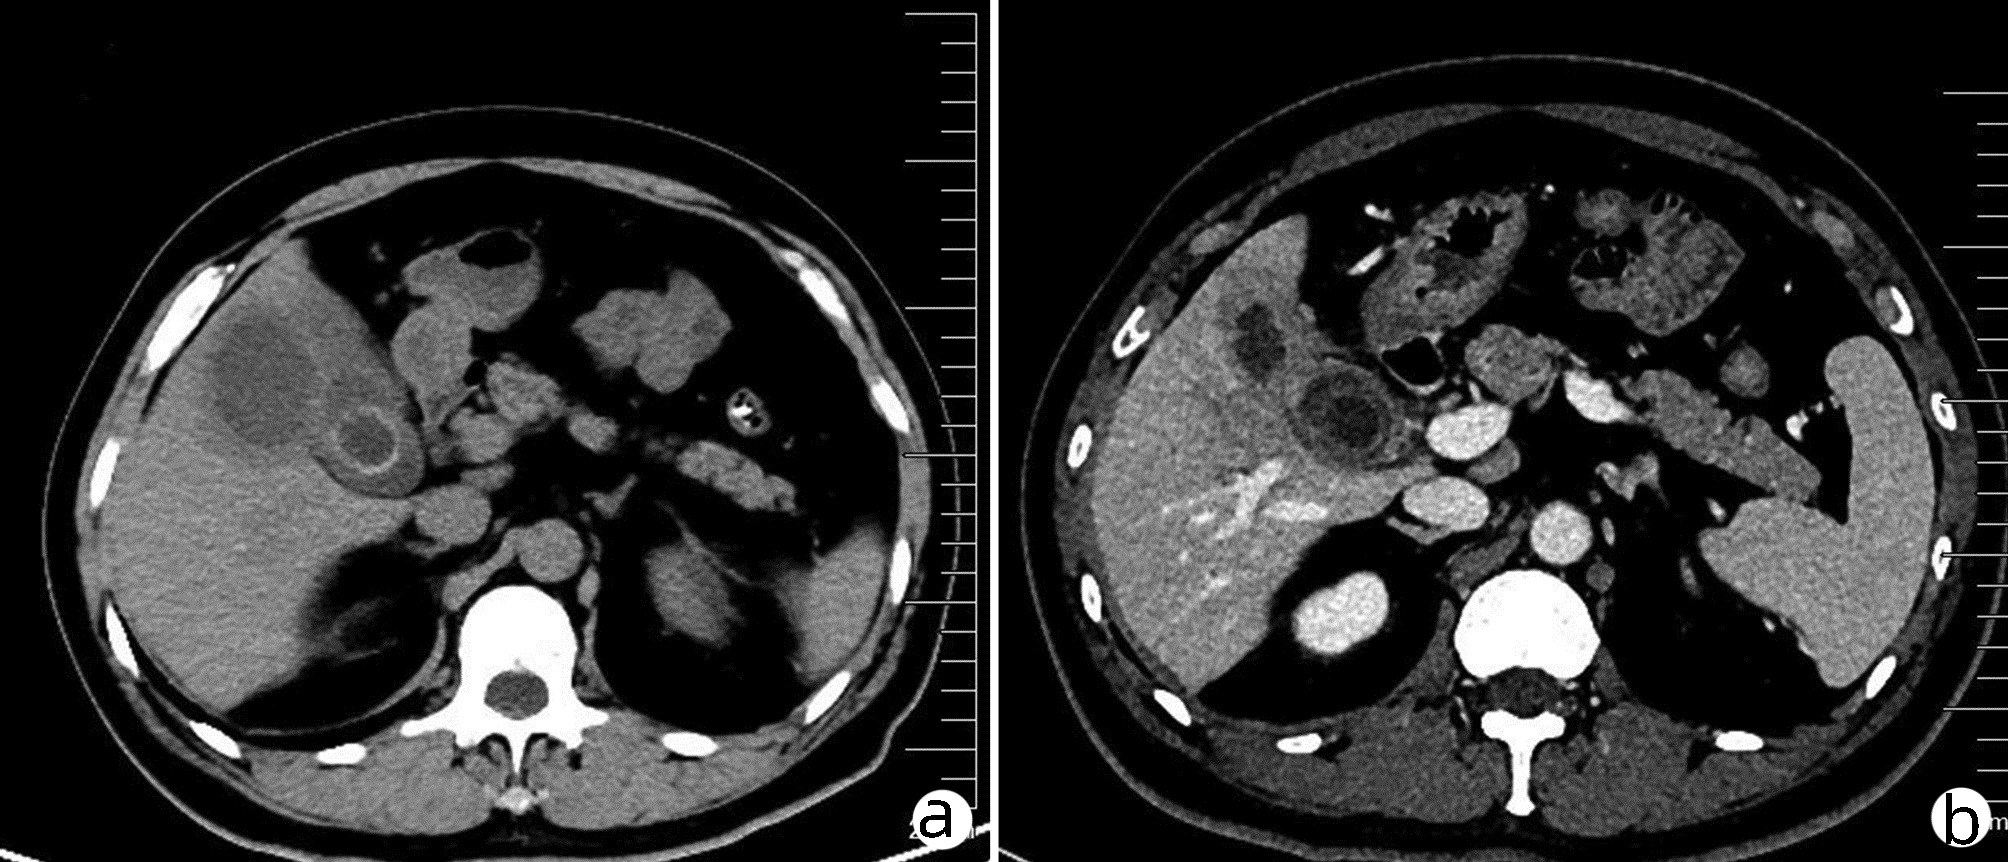

以肝损害为主要表现的嗜酸粒细胞增多症1例报告

吴昊, 郑欣, 朱磊, 杨冬

2022, 38(4): 883-885. DOI: 10.3969/j.issn.1001-5256.2022.04.027

摘要(2117) HTML (304) PDF (2636KB)(145)

摘要: